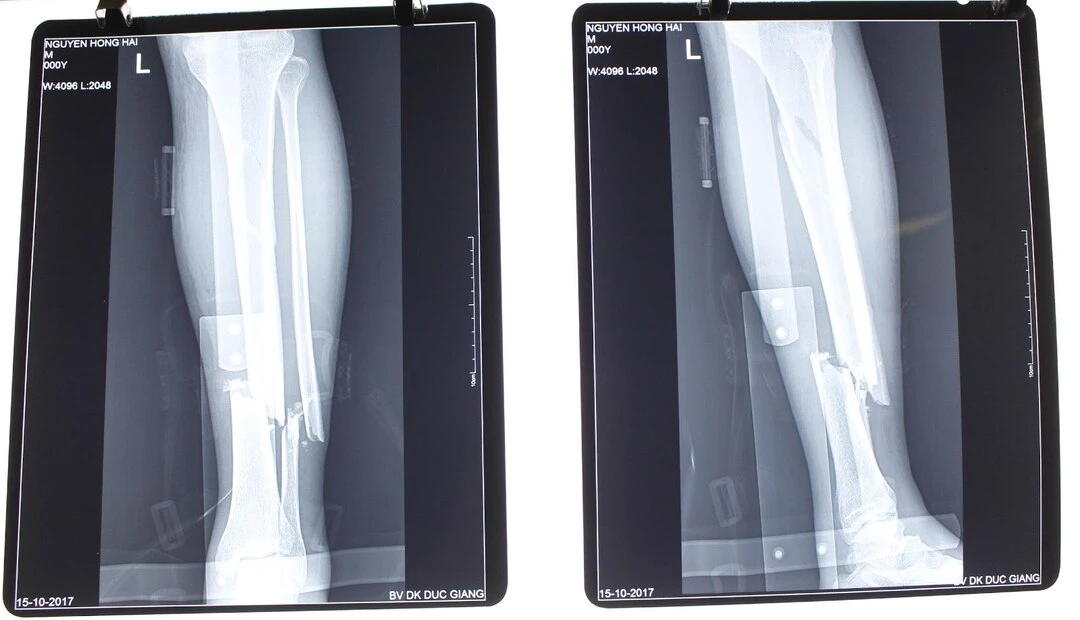

Chụp X-quang

Là phương pháp cơ bản nhất, giúp xác định dạng gãy và mức độ tổn thương.

Điều trị phẫu thuật

Được chỉ định khi có biến chứng hoặc gãy xương phức tạp. Bác sĩ sẽ tiến hành sắp xếp lại xương và cố định bằng ốc vít, mảnh kim loại.